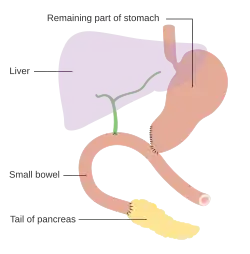

Nos cancros que envolvem a cabeça do pâncreas, o procedimento de Whipple é o tratamento cirúrgico curativo mais comum. Esta operação consiste na remoção em simultâneo da cabeça do pâncreas e da curva do dudodeno ("duodenopancreatectomia"), na criação de um bypass para os alimentos desde o estômago até ao jejuno ("gastro-jejunostomia") e na ligação do jejuno ao ducto cístico para drenar a bílis ("colecisto-jejunostomia"). Este procedimento só pode ser realizado caso a pessoa tenha condições de sobreviver a uma intervenção cirúrgica de risco e quando o cancro não invade estruturas locais ou apresenta metástases, pelo que só é possível numa minoria de casos. Os cancros da cauda do pâncreas podem ser removidos através de um procedimento denominado pancreatectomia distal, que em muitos casos implica também a remoção do baço.[2][3] Hoje em dia, este procedimento pode ser feito através de métodos minimamente invasivos.[2][3]